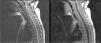

Here, we report a 3.5-year-old girl who presented with ataxia and vomiting and had a diagnosis of primary diffuse leptomeningeal glioneuronal tumor with remarkable brain MRI findings as diffuse multiple tiny cystic lesions on the brain and spinal cord. She benefited from radiotherapy and temozolomide treatment with remission of brain MRI findings.